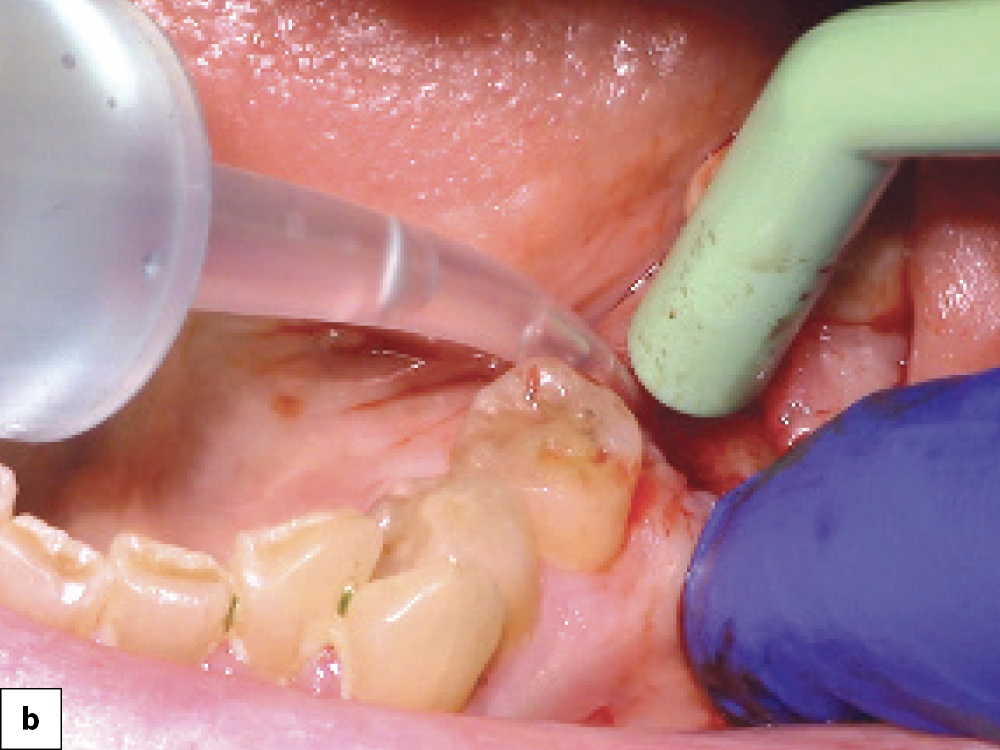

Technique A Severed Periodontal Ligament

Technique B Multi-rooted Tooth

Atraumatic extraction technique: (a) Severing the periodontal ligament fibers, which results in mobilty of the tooth; (b) Multi-rooted teeth should always be sectioned prior to removal to avoid damaging the socket walls.